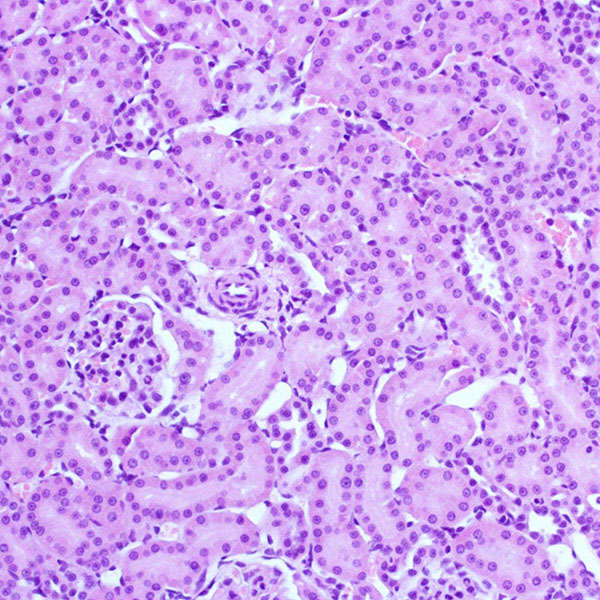

HE染色法